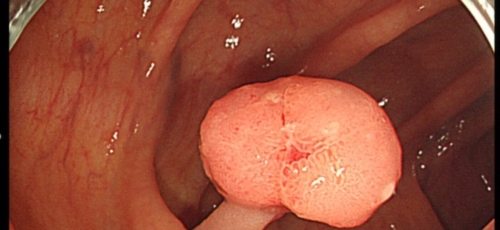

대장내시경

대장암을 초기에 발견해 내려면 대장내시경은 필수인데요 적어도 2년에 한 번 대장내시경을 받아 이상이 없나 확인해 봐야 합니다.CT촬영으로 혹이 보이거나 하는 경우가 있는데요, 사실 초기에 CT로 혹을 잡아내기는 매우 힘들다고 해요. 가장 정확한 건 의사가 눈으로 볼 수 있는 대장내시경이니 건강검진시 꼭 받으시기 바랍니다.

대장내시경의 필요성

대장암 초기증상은 만성복통과 소화불량, 식욕저하, 변비, 설사 등의 다양한 형태로 나타날 수 있습니다. 하지만 초기에는 이렇다할 증상이 보이지 않아 건강검진을 하면서 우연히 발견되기도 합니다. 따라서 대장암을 조기에 발견하고 적기에 치료하기 위해서는 대장내시경 검사를 정기적으로 받는 방법뿐인데요 45세부터는 5년에 한 번씩 대장내시경 검사를 받도록 권장되고있는데, 만약 가족 중 대장암환자가 있거나 유전적 요인이 있는 경우에는 40세부터 정기적으로 검사받는것이 좋습니다.

특이 증상이 없더라도 국가에서 권장하고있는 건강검진 시기에 맞게 대장내시경을 하는 것이 좋습니다. 또한 이러한 증세가 나타난다면 빠른 시일 내에 진료를 통한 내시경 검사를 진행하여 정확한 진단과 그에 맞는 치료가 진행되어야 합니다. 꼭 대장암 초기증상이 아니더라도 대장질환이나 위장질환으로 인해 상황이 악화되어 나타날 수 있기때문에 그냥 넘기지않고 꼭 내원하여 적절한 치료를 받는것이 좋습니다.